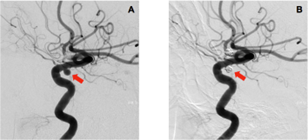

La rupture d’un anévrisme artériel cérébral est la principale cause d’hémorragie méningée. L’anévrisme artériel correspond à une zone de fragilité de la paroi responsable d’une dilatation localisée de la paroi d’une artère aboutissant à la formation d’une poche de taille variable, communiquant avec l’artère au moyen d’une zone rétrécie que l’on nomme le collet (Fig. 1). Le siège de prédilection des anévrismes intracrâniens est situé sur les bifurcations des grosses artères de la base du crâne, au niveau du polygone de Willis. Le principal facteur majorant le risque de rupture est la taille de l’anévrisme.

Fig. 1 : Artériographie cérébrale montrant un anévrisme artériel de l’artère carotide interne (A) et sa guérison après embolisation (B) (flèche)